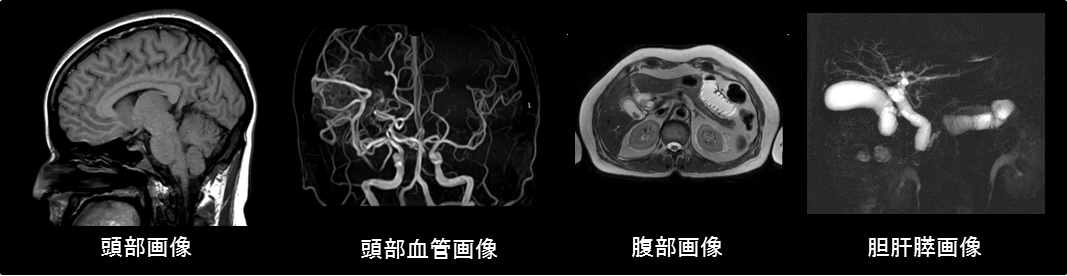

MRI画像

MRI装置は、X線CT装置などと異なり放射線を使用しないため、人体への影響が少なく、人体のあらゆる方向の断面画像を得ることができます。

また造影剤を使用することなく血管を描出することが可能な最先端の画像診断装置です。